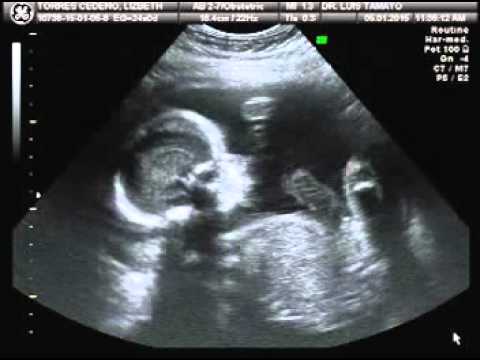

eco 24 semanas de gestacion - YouTube

eco 24 semanas de gestacion - YouTube from i.ytimg.com. Para más información pulse aquí para ir al website.